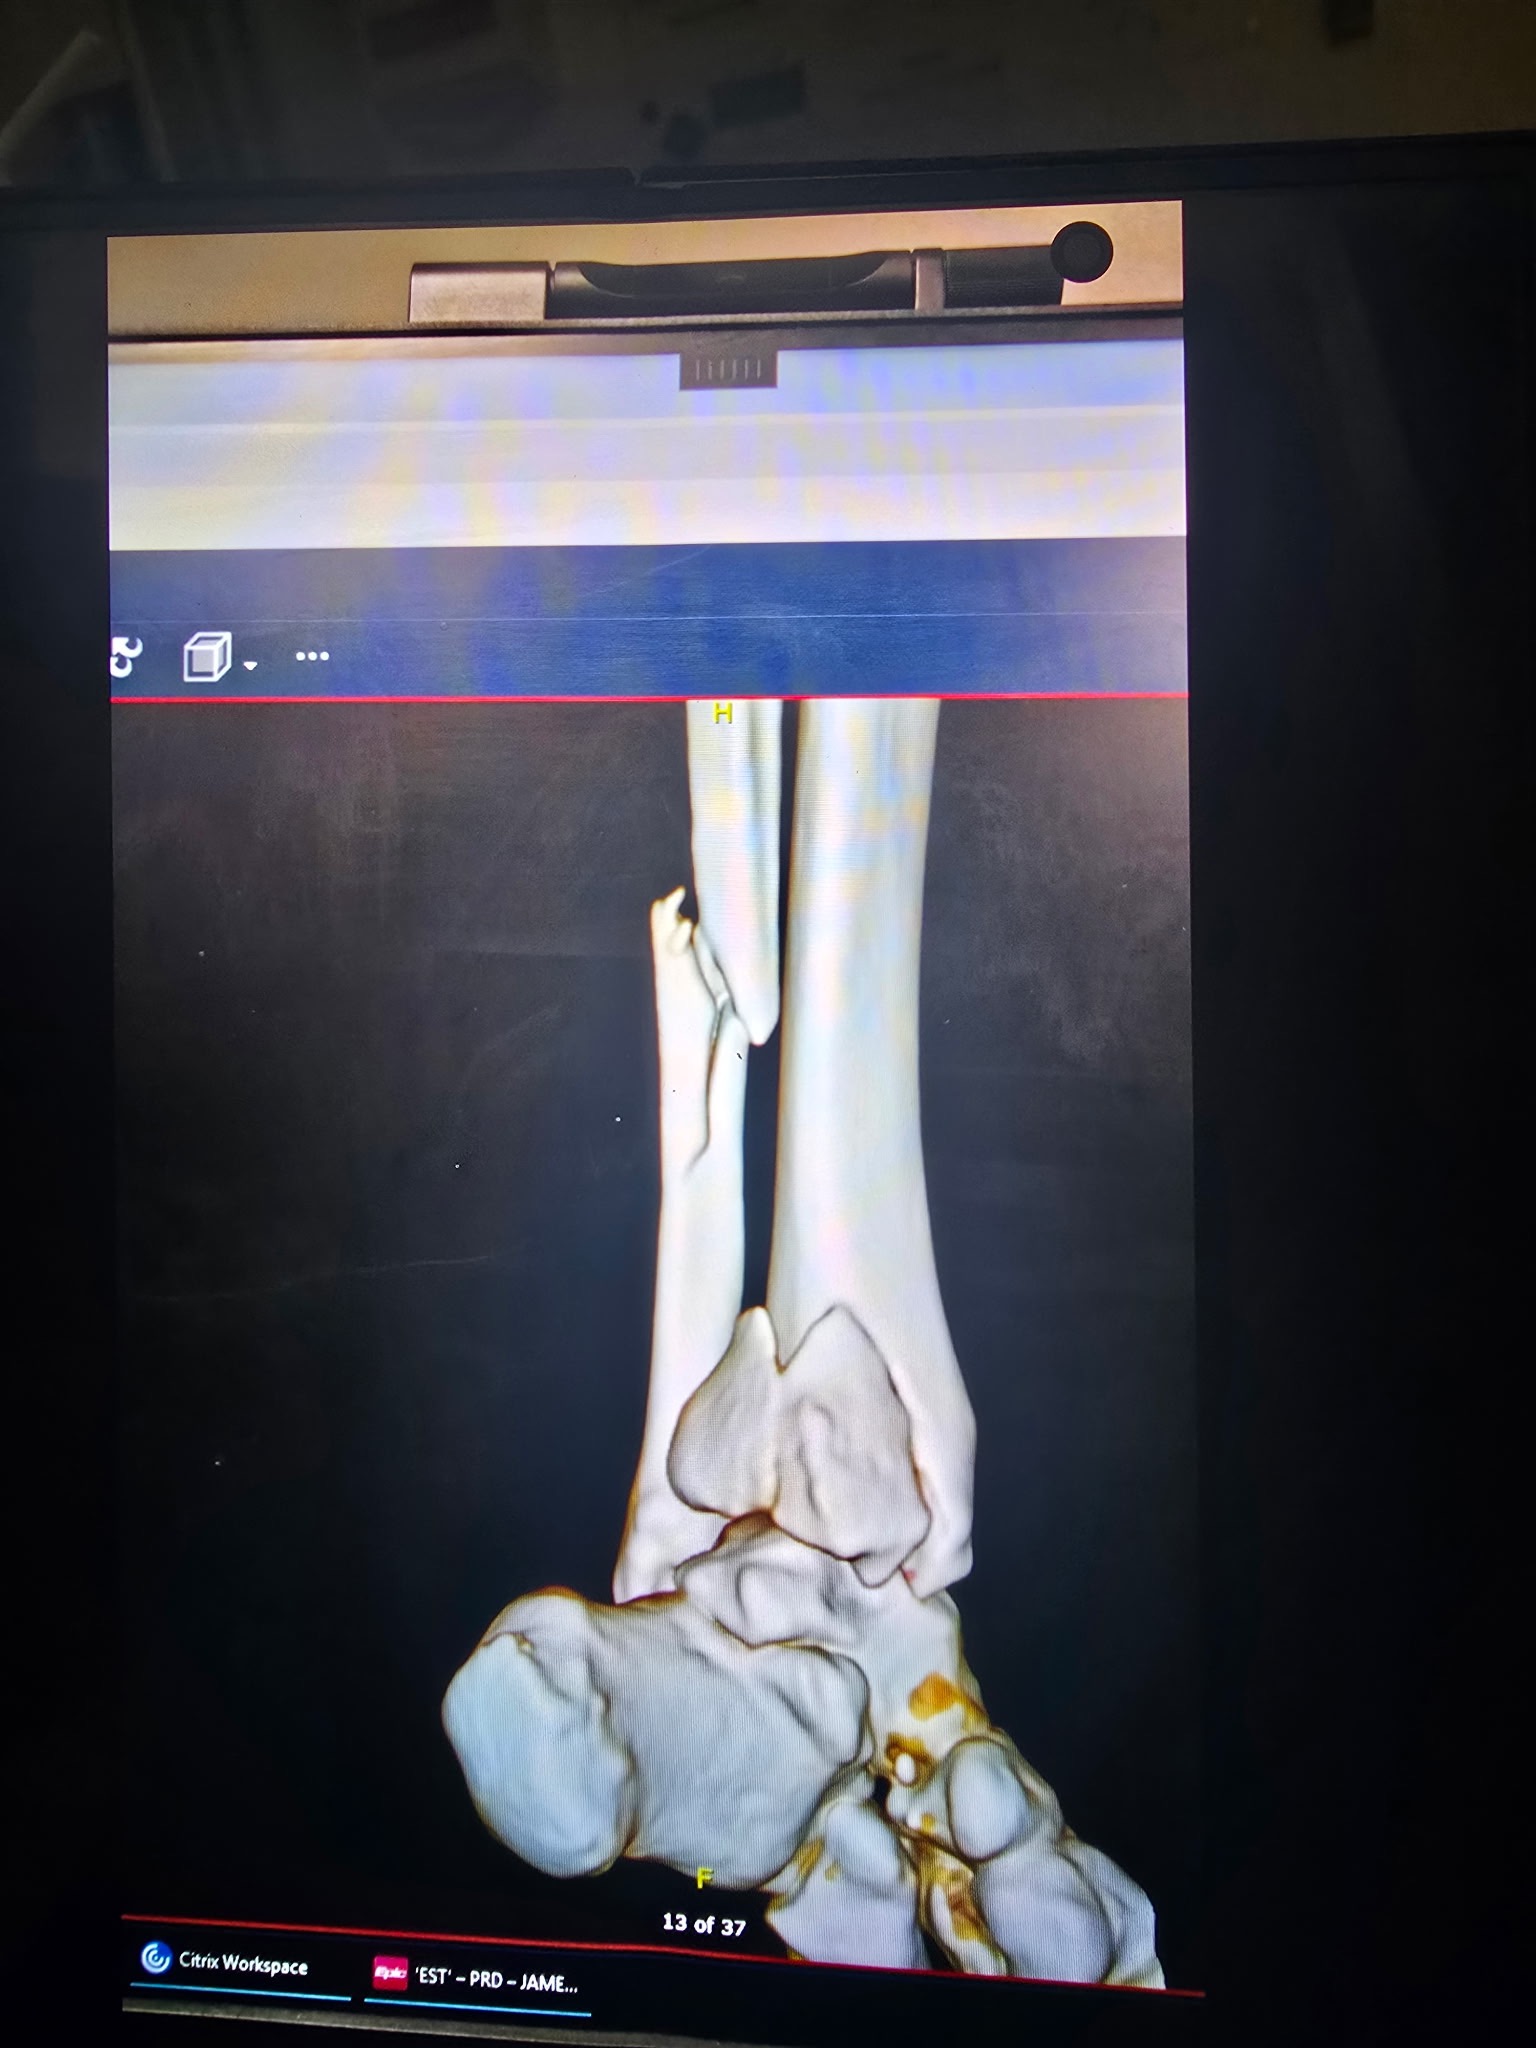

On 01/10/2026, Chelsea slipped and fell on the ice in her driveway, causing a dislocated ankle along with fractures to her ankle and leg. She went to the ER the same day, where the dislocation was stabilized, and she was admitted to the hospital. On 01/11/2026, she underwent her first surgery, where a rod, plate, and screws were placed to stabilize her injuries.

At her follow-up appointment with her orthopedic surgeon on 01/14/2026, it was determined that there had been too much swelling during the first surgery, and she would need a second surgery to place an additional plate on the back of her ankle. That second surgery was completed on 01/15/2026.